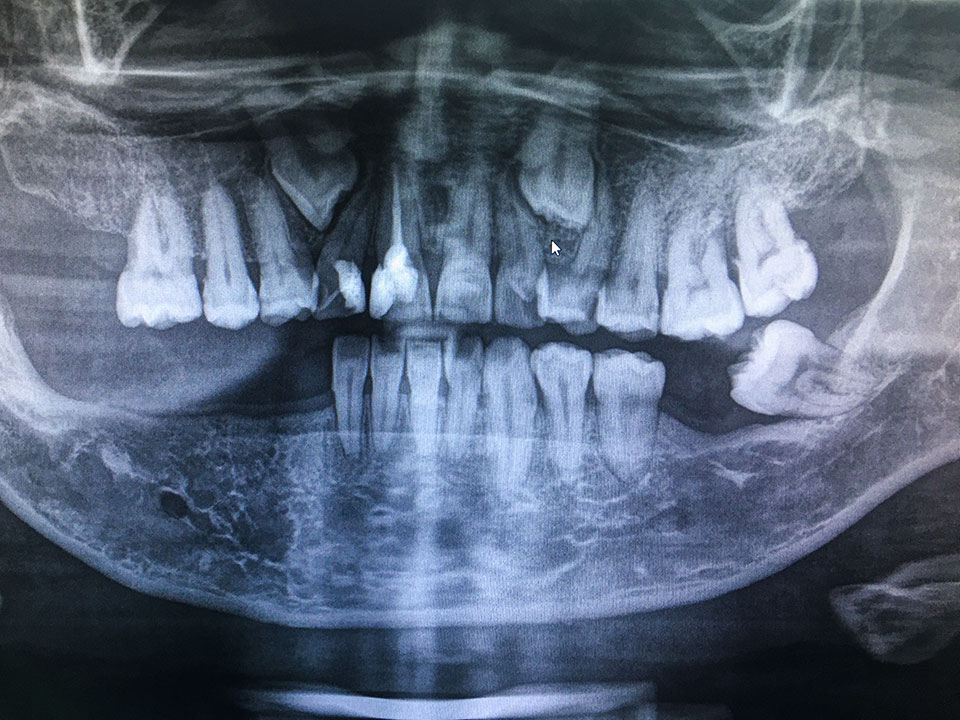

Bei der Aufnahme fährt der Röntgenkopf einmal im Halbkreis um Ihren Kopf herum. Dabei nimmt sie schichtweise das gesamte Gebiss auf. Die Aufnahme zeigt alle Zähne im Ober- und Unterkiefer, den Kieferknochen sowie die beiden Kiefergelenke und die Kieferhöhlen rechts und links.

Die Panorama-Schichtaufnahme gibt einen guten Gesamtüberblick über den Kauapparat. Sie zeigt, ob es retinierte Zähne gibt, d.h. solche, die noch nicht oder nicht ganz durchgebrochen sind, oder verlagerte Zähne, die am falschen Platz stehen oder in die falsche Richtung wachsen. Solche Probleme kommen häufig bei Weisheitszähnen vor. Weicht ein Zahn von seiner normalen Achse ab und schiebt sich dabei gegen einen Nachbarzahn, kann das dessen Wurzel beschädigen. Auszumachen sind auch Veränderungen des Kieferknochens, der Kieferhöhlenschleimhaut, an Nerven oder Gefäßen.

So können wir potenzielle Probleme frühzeitig erkennen und gefährdeten Zähnen mit kieferorthopädischen oder chirurgischen Maßnahmen helfen. Vor dem Setzen von Zahnimplantaten bestimmen wir die optimale Position für die neuen künstlichen Zahnwurzeln.